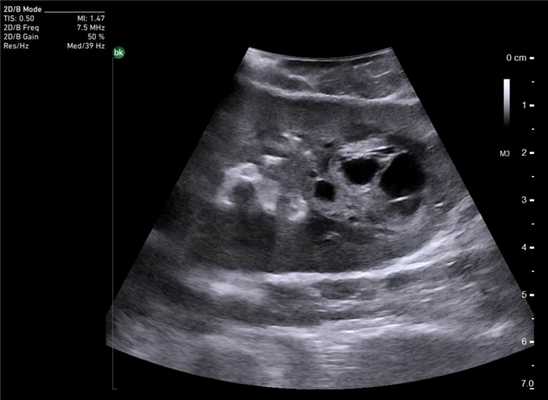

Клинический пример N1. Пациент М. находился на лечении в ГУРОНЦ РАМН, с диагнозом: рак сигмовидной кишки. При проведении дооперационного обследования была выполнена компьютерная томография, и дано заключение о наличие метастатического поражения печени. Однако при ультразвуковом исследовании осмотр печени был затруднен, вследствие перекрытия печени петлями кишки и выраженного метеоризма. При интраоперационной ультразвуковой ревизии подтвердилось метастатическое поражение обеих долей печени.

Клинический пример N2. Пациентка Р. находилась на лечении в ГУРОНЦ РАМН. При прохождении обследования был установлен диагноз рак толстой кишки. По данным ультразвуковой компьютерной томографии на фоне выраженной диффузной неоднородности паренхимы печени очаговые образования не определялись. При проведении ангиографии и компьютерной томографии так же убедительных данных за наличие метастазов в печень получено не было. При интраоперационном ультразвуковом исследовании были выявлены два очага, характерными особенностями которых являлись малые размеры (0,2 - 0,4 см), а так же нечеткость контуров и изоэхогенность структуры (рис. 1 а,б).

Рис. 1. Метастатические очаги (стрелки) в печени при интраоперационной ультразвуковой томографии.